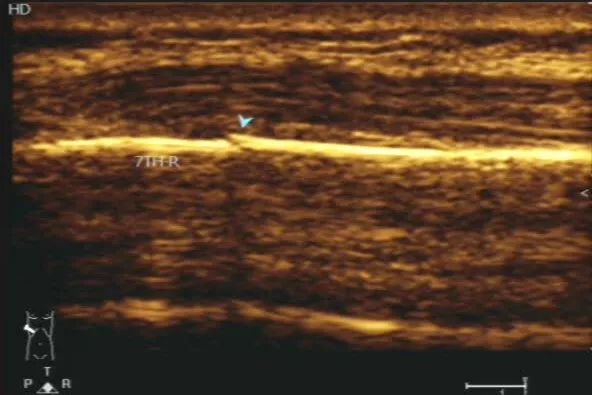

65岁男性患者,碰伤致右胸腹疼痛四天,右胸腹压痛。经肌骨超声检查后提示考虑第七肋骨线性骨折伴软组织肿胀。